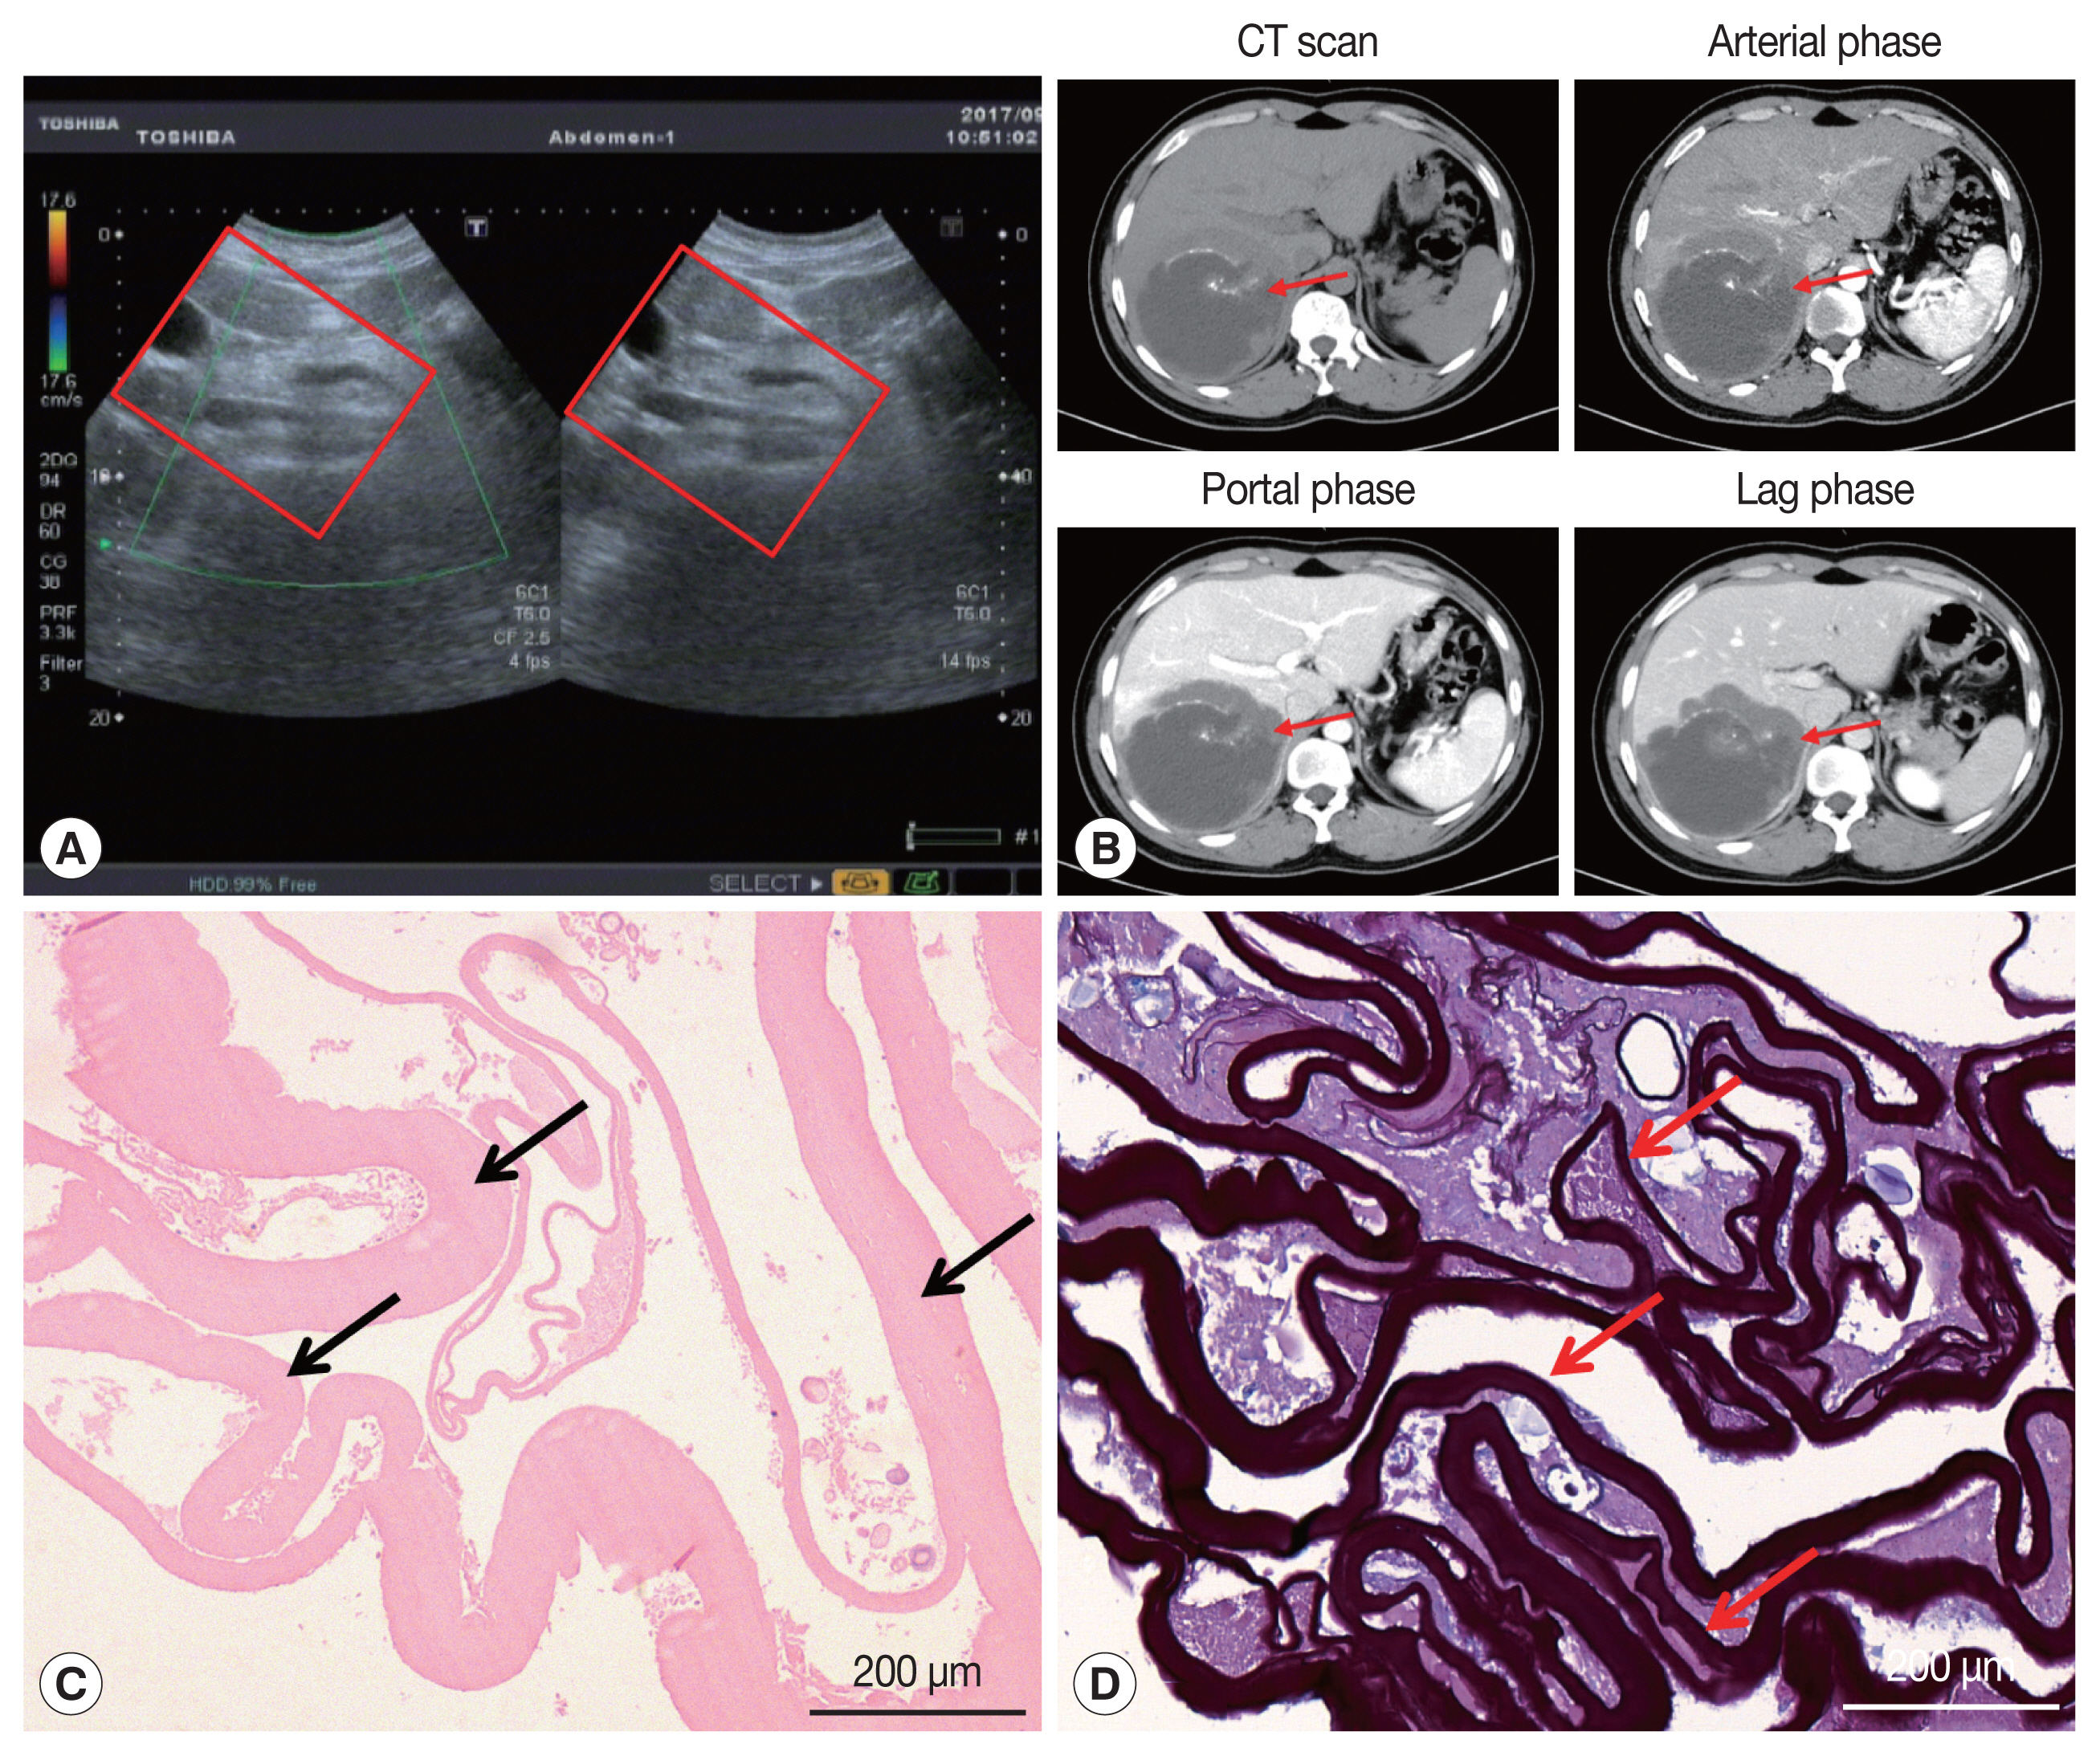

On January 3, 2017, a 34-year-old Tibetan Chinese man came to the Department of Neurosurgery at the Qinghai University Affiliated Hospital for treatment with severe upper abdominal pain. The patient lived in pastoral areas of Qinghai Province for a long time and had been in good health before. Physical examination touched a mass in the upper abdomen, which was 18.0×16.0 cm in size, accompanied by tenderness. Ultrasound Color Doppler of the upper abdomen presented a 11.6×11.2 cm mixed mass in the right posterior lobe of the liver (Fig. 1A). The dynamic 3-phase Computed Tomography (CT) examination of the liver demonstrated a round lesions (about 9.6×8.9 cm) in the liver S7-6 segment, with a thick wall, and a CT value of about 16 HU. Calcification could be observed in the lesion, and no enhancement was seen in the lesion after enhancement (Fig. 1B). Chest X–ray and laboratory findings were all within normal limit. Additionally, hydatid serological IgG ELISA remained negative. Stool examination showed no parasites or eggs. Based on these findings, the patient was diagnosed as hepatic AE. The patient underwent right hepatectomy and cholecystectomy on September 6, 2017. During the operation, there existed obvious adhesion between the lesion and the lateral abdominal wall, which invaded the diaphragm and lateral peritoneum. Postoperative pathological examination confirmed AE disease. The histopathological examination showed obvious laminated layer (Fig. 1C), intensely colored by the periodic acid-Schiff stain without a germinal layer (Fig. 1D). These morphological findings verified AE. The patient fully recovered after surgery. The patient was treated with albendazole (400 mg twice a day) orally for 2 year.